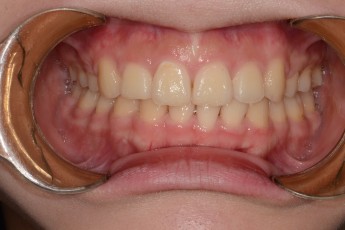

Before

After